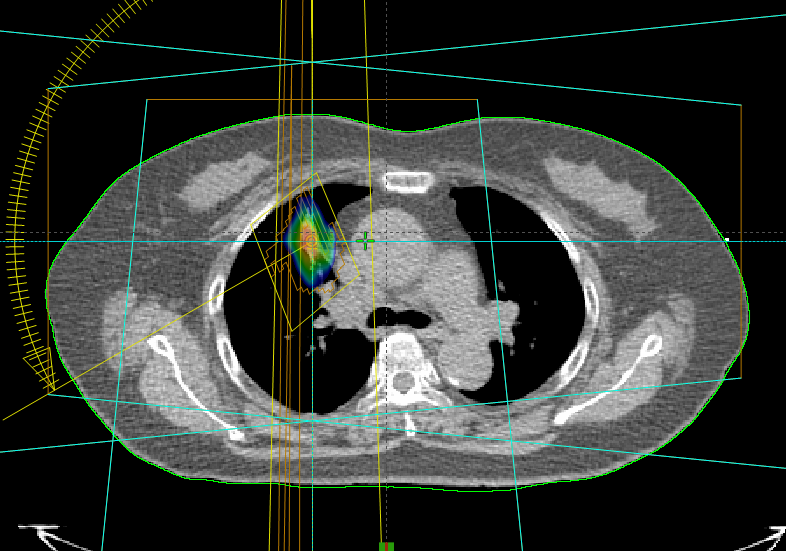

立體定位放射治療技術的特點是極高精準度,治療療程為高劑量、少次數。因為治療次數少,治療天數大幅縮短;因為極高精準度及單次劑量高,治療副作用輕微且療效佳(臨床適用於早期肺癌、肝腫瘤或低數量轉移、腦部轉移或腫瘤、或是轉移腫瘤,詳細相關適應症需諮詢放射腫瘤科醫師),下方案例為早期肺癌及肝腫瘤立體定位放射治療。

案例一 早期肺癌立體定位放射治療